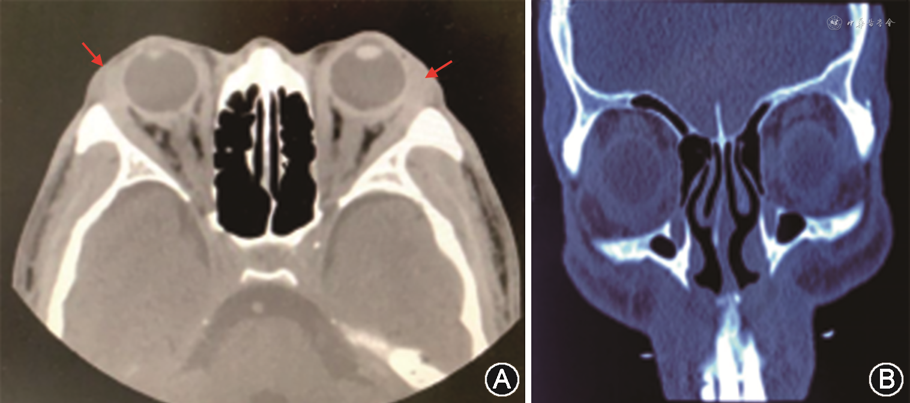

追问病史,患者曾于8个月前因双眼球突出伴眼红、流泪半年至外院眼科就诊。视力右眼为1.0,左眼为0.8,双眼上睑红肿,泪腺区肿胀,双眼球结膜充血水肿,各直肌止端结膜呈紫红色充血肥厚,双眼眼压及眼底未见异常。眼眶CT提示双眼内、外、上、下直肌均见明显增粗,边缘模糊,眶内脂肪间隙模糊,泪腺肿大(图2中A)。外院诊断为双眼眶炎性假瘤,予以地塞米松10 mg静脉滴注1次,后改为醋酸泼尼松80 mg/次、1次/d口服,并逐渐减量。治疗6个月后患者症状好转,复查眼眶CT,可见双眼内外、上下直肌稍增粗,边缘清晰,泪腺肿大较前好转(图2中B)。